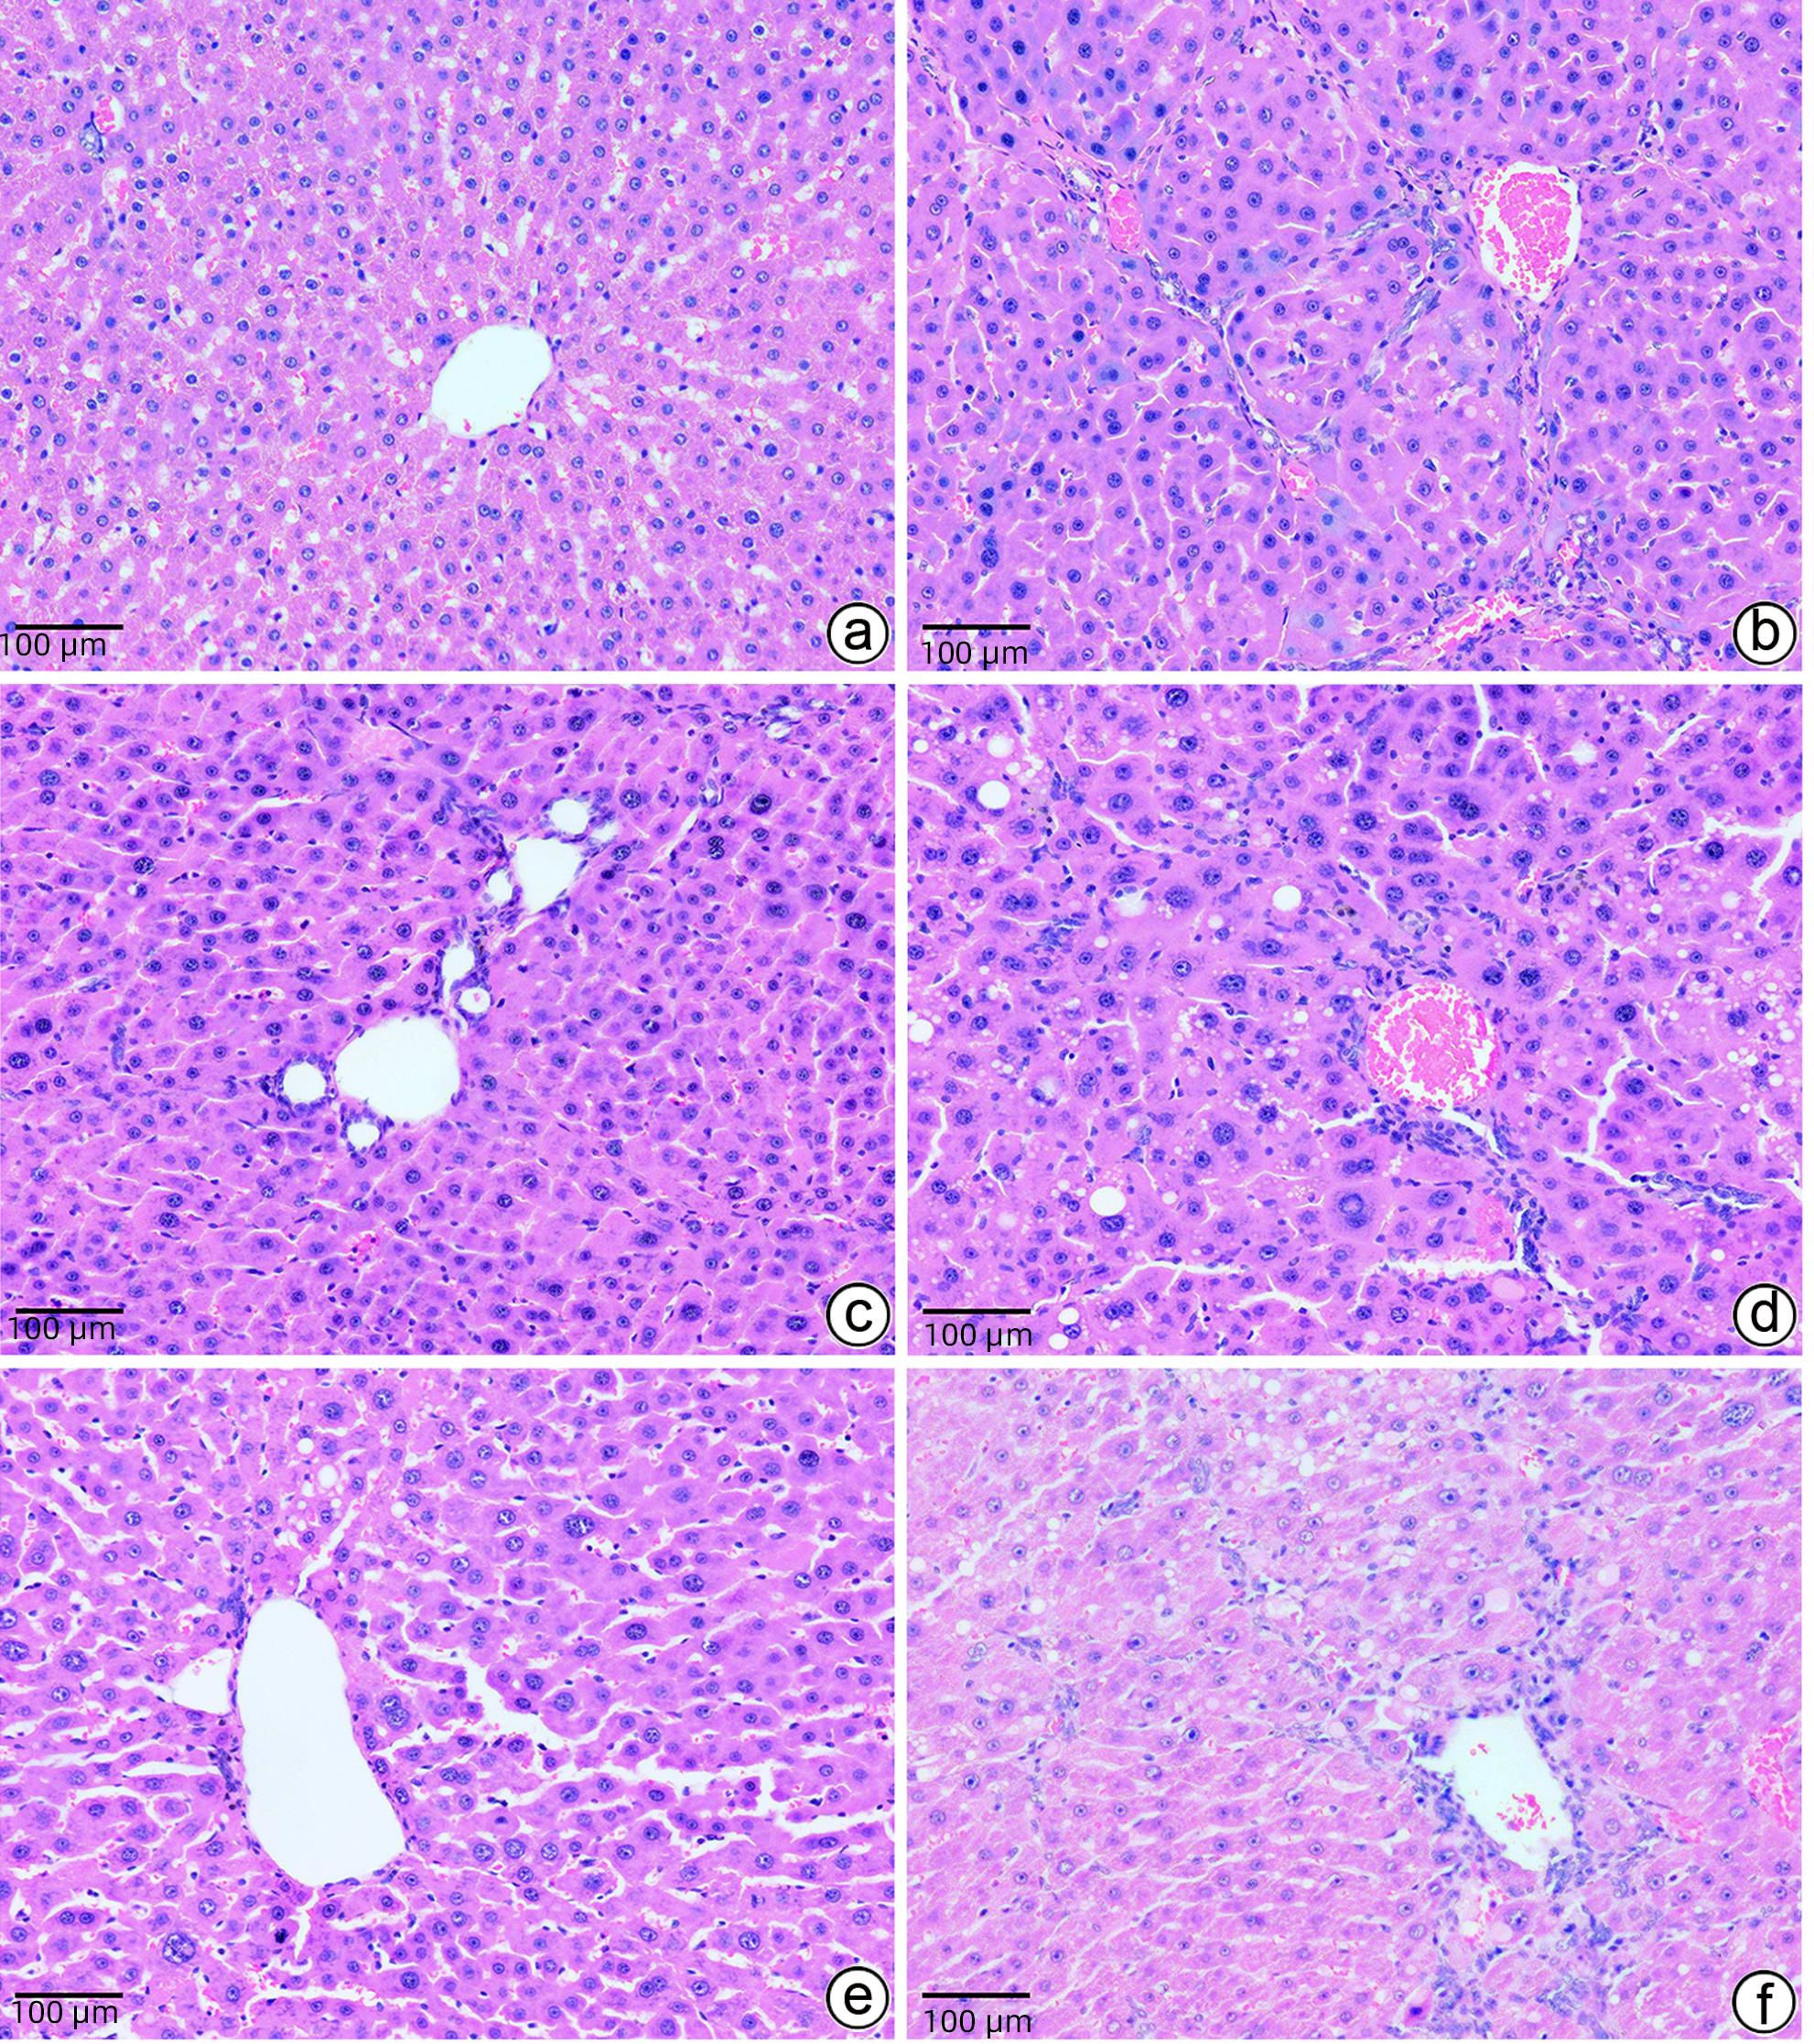

基于PI3K/AKT/mTOR信号通路探讨大黄煎剂对轻微型肝性脑病大鼠脑组织炎症损伤的保护机制

2024, 40(2): 312-318. DOI: 10.12449/JCH240215

摘要(1155) HTML (450) PDF (1982KB)(73)

摘要:

目的  探讨大黄煎剂保留灌肠对轻微型肝性脑病(MHE)大鼠模型脑组织炎症损伤的改善作用及可能机制。  方法  60只SD雄性大鼠按完全随机方法分为空白组(CON组,n=6)和慢性肝硬化造模组(n=54)。12周后慢性肝硬化造模成功并经Morris水迷宫测试确认符合MHE模型大鼠40只,采用完全随机方法分为模型组(MOD组,n=8)、乳果糖组(LT组,n=8)、大黄煎剂低剂量组(RD1组,n=8)、大黄煎剂中剂量组(RD2组,n=8)和大黄煎剂高剂量组(RD3组,n=8)。其中CON组和MOD组大鼠用生理盐水保留灌肠,2 mL/只,1次/d;LT组大鼠用乳果糖按22.5%剂量保留灌肠,2 mL/只,1次/d;RD1组、RD2组、RD3组大鼠分别用大黄煎剂按2.5、5.0、7.5 g/kg三种剂量保留灌肠,2 mL/只,1次/d。所有大鼠治疗10 d后,进行Morris水迷宫测试,分析大鼠的空间学习记忆能力。分析大鼠行为学状态;检测大鼠血清ALT、AST、IL-1β、IL-6、TNF-α和血氨水平;观察大鼠肝组织和脑组织病理学变化;检测大鼠脑组织磷脂酰肌醇3-激酶(PI3K)、蛋白激酶B(AKT)、雷帕霉素靶蛋白(mTOR)的mRNA和蛋白表达水平。计量资料多组间比较采用单因素方差分析,进一步两两比较采用LSD-t检验。  结果  与MOD组比较,RD1组、RD2组和RD3组大鼠逃避潜伏期时间显著缩短(P值均<0.01),ALT、AST、IL-1β、IL-6、TNF-α和血氨水平明显降低(P值均<0.05),肝细胞、脑细胞变性、坏死和炎症程度减轻,脑组织PI3K、AKT、mTOR的mRNA和蛋白表达水平均降低(P值均<0.05),且RD3组治疗效果优于RD1组和RD2组。  结论  大黄煎剂保留灌肠能够改善MHE大鼠认知功能及脑组织炎症损伤,其作用机制可能与调控PI3K/AKT/mTOR信号通路有关。